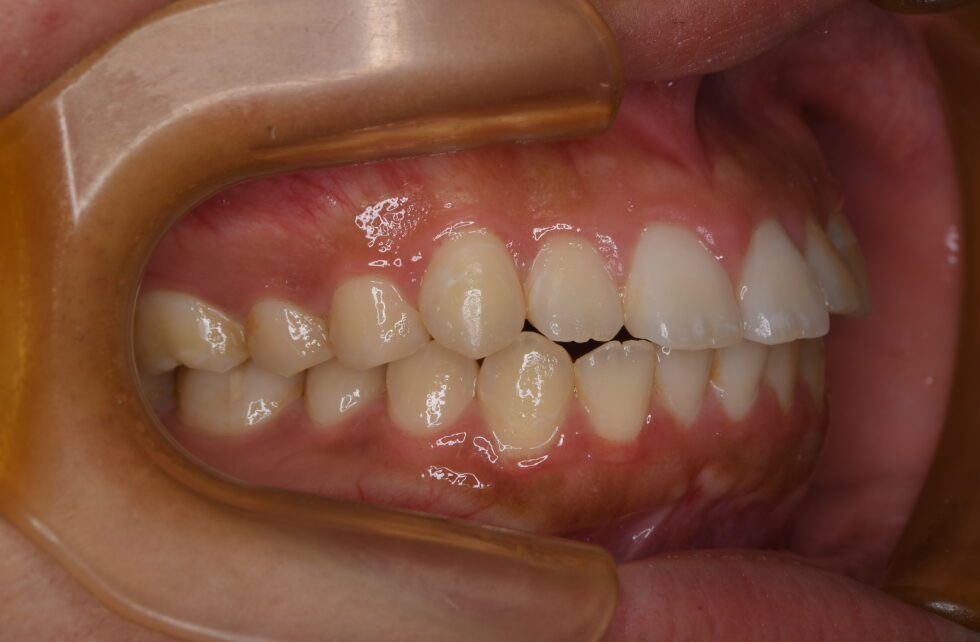

初診時年齢18歳の女性。叢生を伴う上下顎前突のケース

口元の突出および前歯の前傾を気にしておられました。審美的な矯正装置を希望されたため上顎舌側(裏側)・下顎唇側マルチブラケット装置を使用して、上下顎左右側小臼歯の抜歯による動的治療を行いました。前歯の前傾を改善し、口元の形態を整えることが出来ました。

動的治療期間は3年5ヶ月間